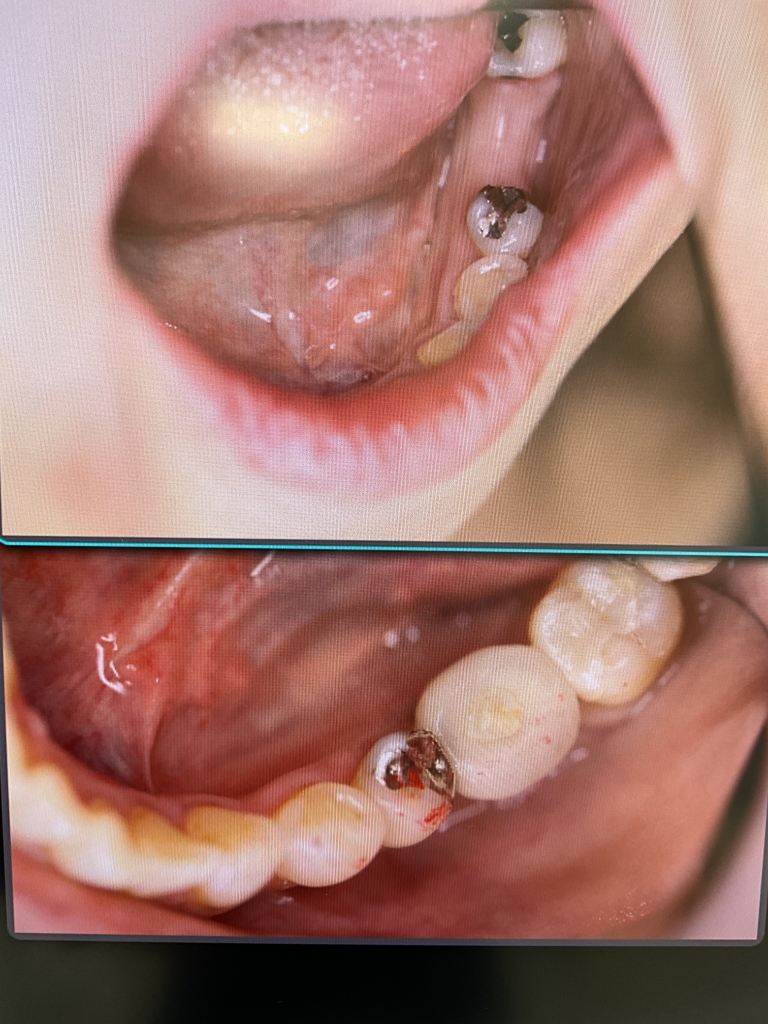

いつまでも健康的で若々しく、素敵な笑顔でいられるために、入れ歯や欠損などでお困りの患者さんにインプラント治療をお勧めします。

患者さんが安心して手術を受けていただけるように、CT撮影などの術前検査と十分なカウンセリングを行います。

万が一インプラント治療が適さない症例であれば他の治療法を提案させていただくこともあります。